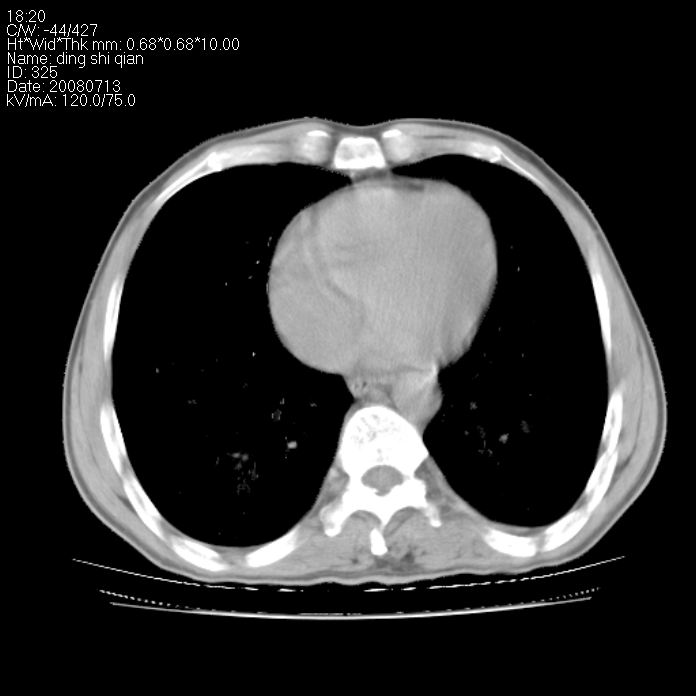

标题: CT14654:男 50岁 近来胸痛 [打印本页]

标题: CT14654:男 50岁 近来胸痛

右侧上肺块状软组织影,浅分叶,边缘毛刺证,与胸膜粘连,考虑:周围性肺癌

右侧上肺块状软组织影,浅分叶,边缘毛刺证,与胸膜粘连,考虑:周围性肺癌!支持!